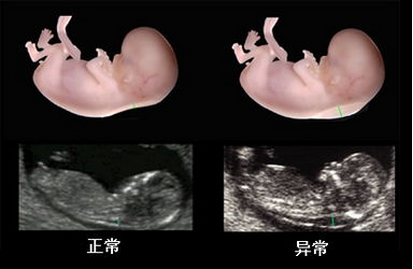

在线咨询系统彩超是孕妈妈非常重要的一项检查, 可以指导优生优育,通过系统检测胎儿生长发育情况。在检查时孕妈妈一定要把握好做系统彩超的黄金时间,那么怀孕多久做系统彩超比较合适呢?

孕早期的系统彩超检查的黄金时间为孕11-14周,这个时候可以通过颈后透明层排除宝宝先天愚型和智力缺陷,而孕晚期系统彩超黄金时间是30--34周,可以对胎儿进行全身系统检查,但具体的检查时间,还是应该根据孕妈妈自身情况来决定,同时,孕妈妈要注意选择一家专业的医院进行系统彩超,才能够达到预期的检查效果。

在检查过程中医生会仔细的对脊椎、头颅、内部、腹部等身体内部各器官进行逐一检查,全面的排查可能存在的异常。

★清晰,排除胎儿先天性疾病:多方位、多角度的观察宫内胎儿的生长发育情况,排除宝宝智力以及先天愚型。